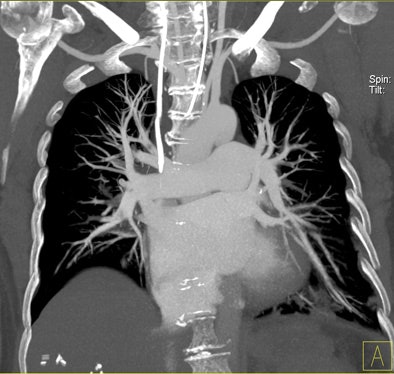

| Patient with bilateral segmental and subsegmental PE and large perfusion defects on dual-energy iodine distribution maps. All images courtesy of Dr. Ralf Bauer. |

Dual-energy CT enables the selective display of iodine distribution within the pulmonary parenchyma following contrast-enhanced pulmonary CT angiography, which in turn permits the calculation of perfusion defect (PD) size in patients with suspected PE.

Depending on the shape and pattern of the defects at dual-energy CT, perfusion defects due to PE can generally be distinguished from, for example, patchy defects signaling other pathologies of the lung parenchyma, Bauer said.

The researchers measured perfusion defect size in the lung parenchyma caused by PE on dual-energy iodine distribution maps, and expressed it in two ways: as absolute quantification (VolPD in mL) and relative to the total lung volume (RelPD in %).